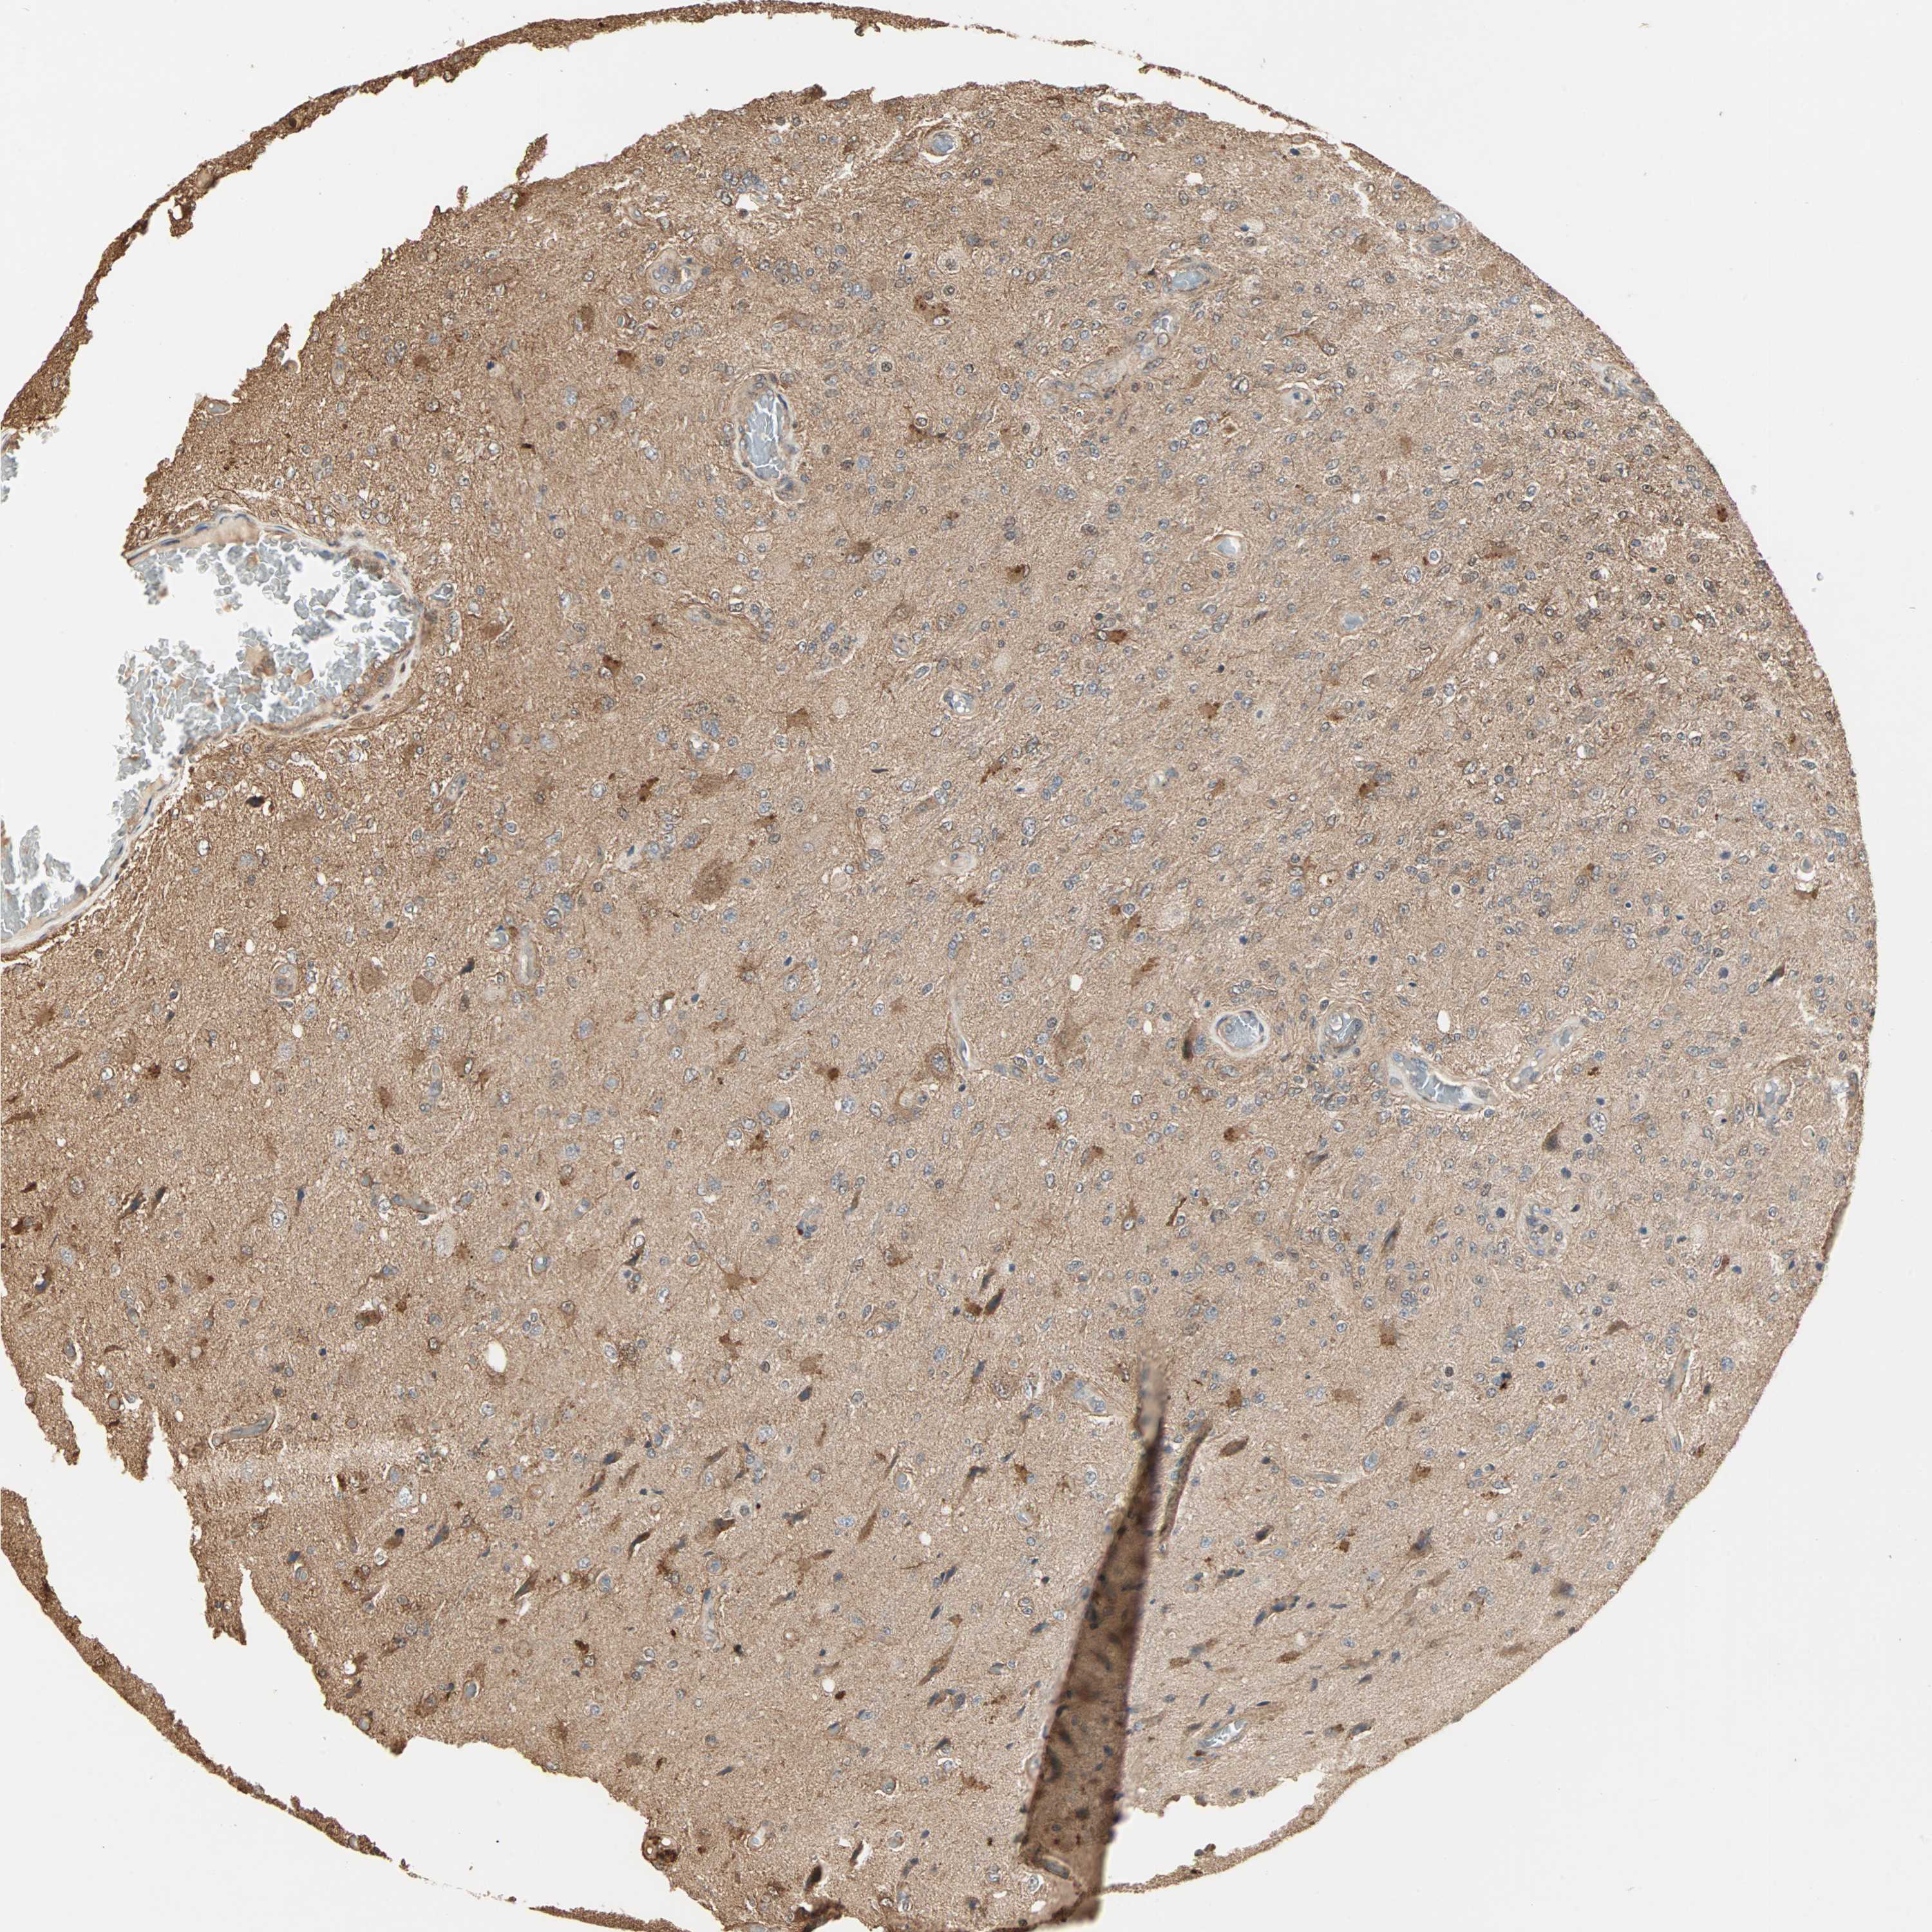

GLIOMA - Protein expressioni

A mouse-over function shows sample information and annotation data. Click on an image to view it in a full screen mode. Samples can be filtered based on level of antibody staining by selecting one or several of the following categories: high, medium, low and not detected. The assay and annotation is described here.

Note that samples used for immunohistochemistry by the Human Protein Atlas do not correspond to samples in the TCGA dataset.

Antibody stainingi

Antibody staining in the annotated cell types in the current human tissue is reported as not detected, low, medium, or high, based on conventional immunohistochemistry profiling in selected tissues. This score is based on the combination of the staining intensity and fraction of stained cells.

Each image is clickable and will lead to virtual microscopy that enables deeper exploration of all samples and also displays staining intensity scores, fraction scores and subcellular localization as well as patient and tissue information for each sample.

Antibody HPA007716

Staining

High

Medium

Low

Not detected

Intensity

Strong

Moderate

Weak

Negative

Quantity

>75%

75%-25%

<25%

None

Location

Nuclear

Cytoplasmic/membranous

Cytoplasmic/membranous,nuclear

Glioma, malignant, Low grade

Glioma, malignant, High grade